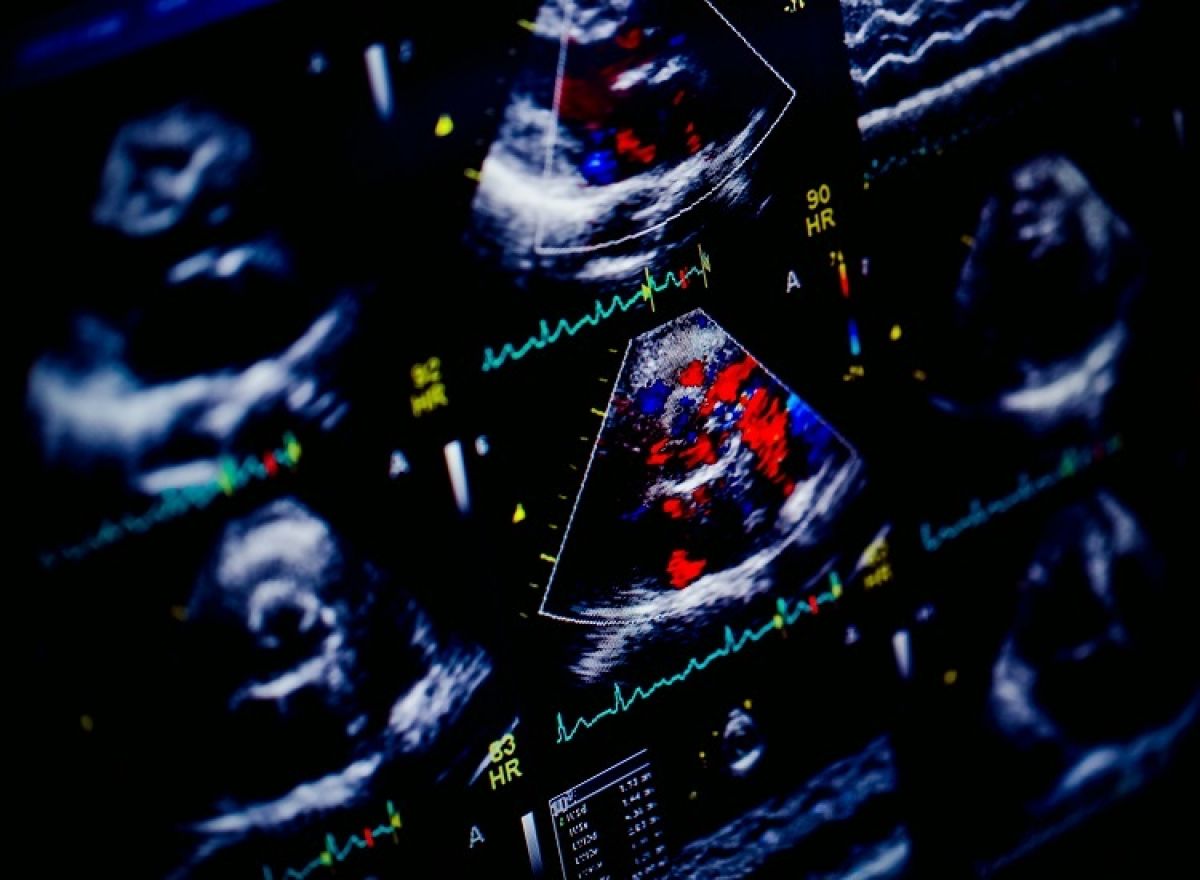

Pacjentka z pogorszeniem tolerancji wysiłku, kołataniami serca i szmerem rozkurczowym; w wywiadzie przebyty udar niedokrwienny mózgu

Złożona wada mitralna – ciężka stenoza i umiarkowana niedomykalność

Echokardiografia przezklatkowa i przezprzełykowa

Ocena stenozy i niedomykalności zastawki mitralnej